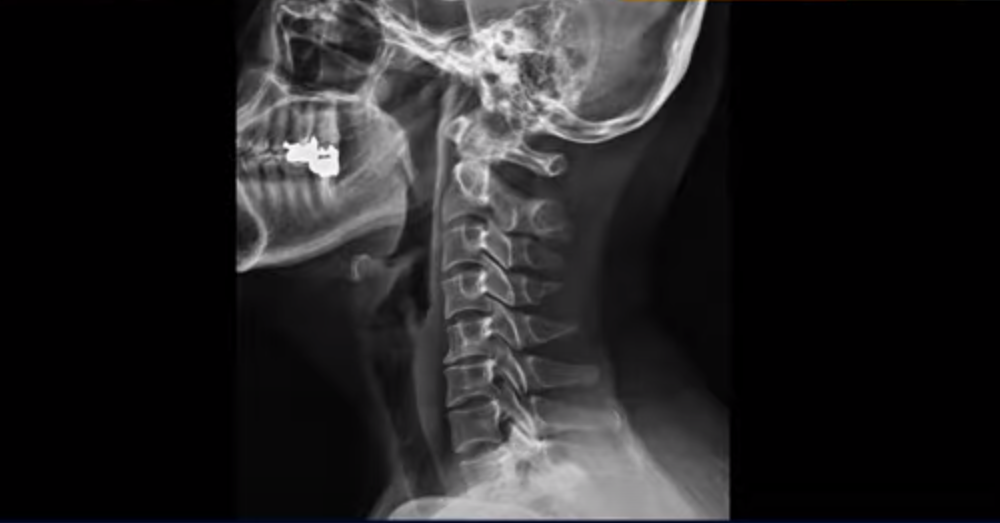

이분 x-ray를 보시면 일자목이고 이런 목 형태에서는 목 주변 근육이 만성적으로 뭉치고 굳고 아픕니다.

그러니까 수년간 만성적인 목 통증이 있었고 항상 목 근육과 승모근이 뭉쳐있고 항상 담 걸린 것 같은 증상이 있는 겁니다. 특히 이런 일자목, 거북목 형태의 목은, 목 앞쪽의 근육들이 더 많이 뭉치고 단축되는데 그러면 목뼈들을 계속 잡아당기니까 신경 눌림이 더 심해질 수밖에 없습니다. 그러니까 잘 쉬면서 2주가 지나도 염증이 잘 가라앉지 않는 겁니다.